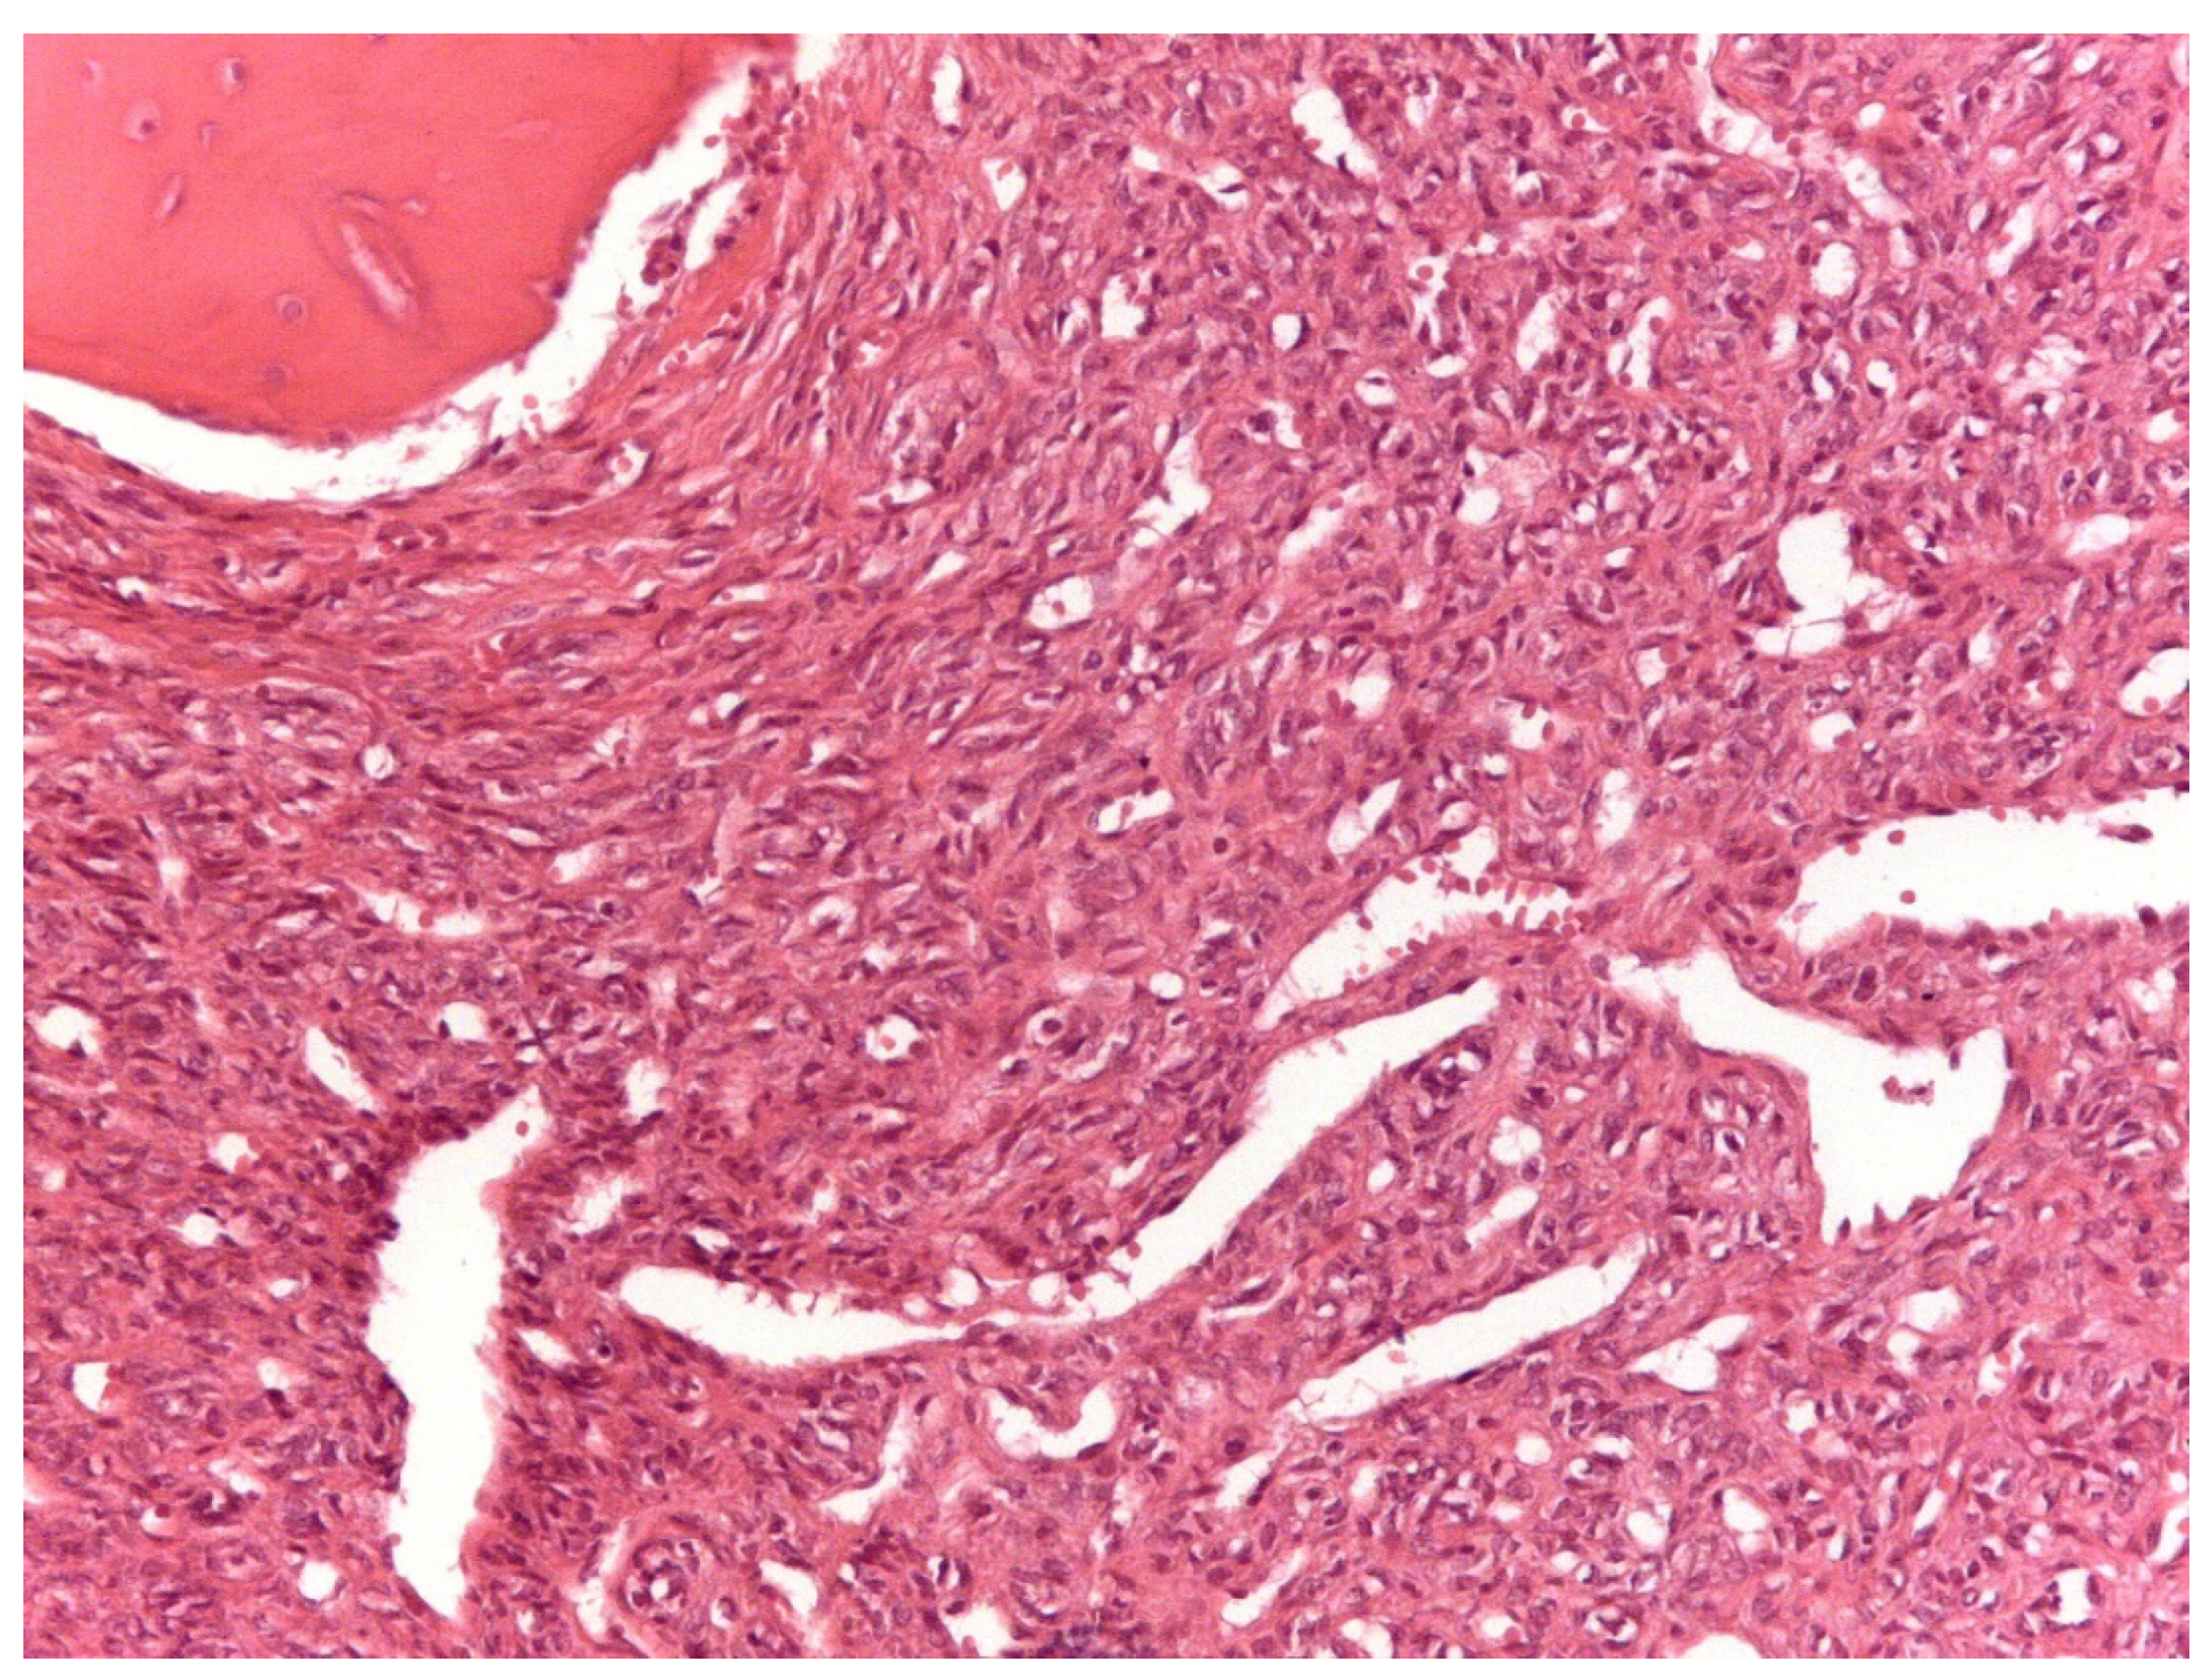

3.2. Histopathological and Immunohistochemical Features